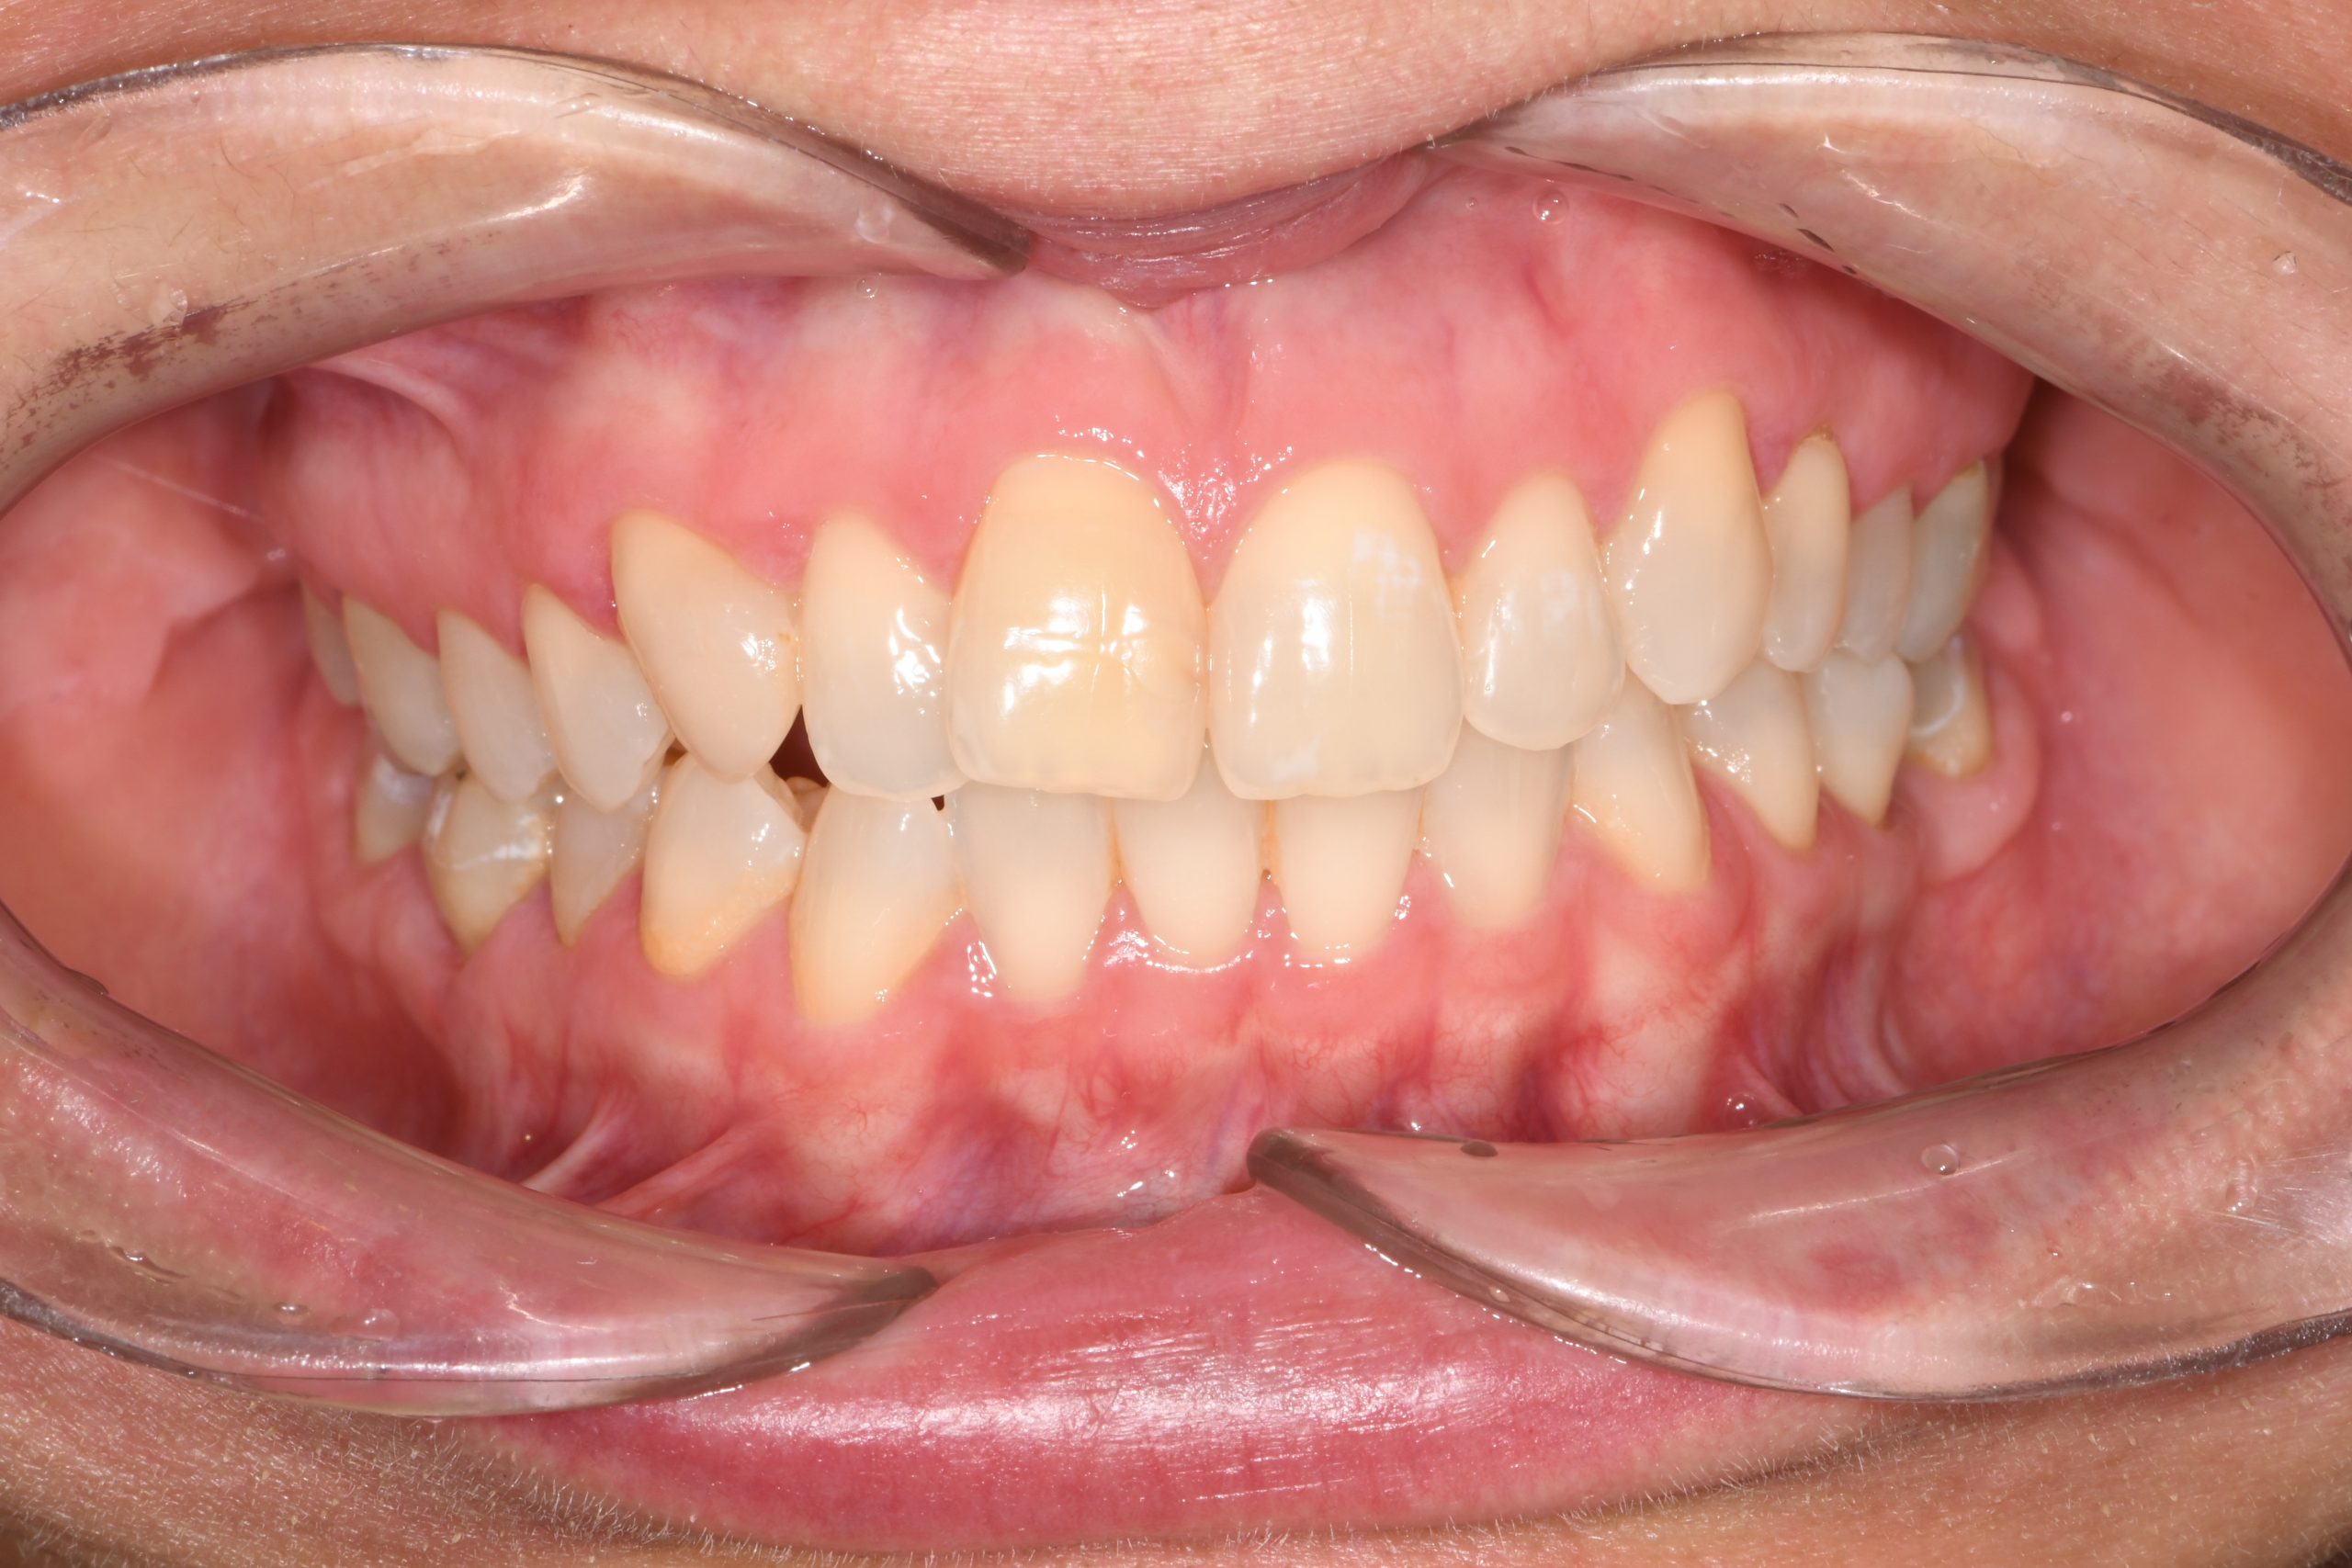

Az elmúlt évekből rengeteg szakmai referenciát tudnánk bemutatni, amelyek különböző fogszabályozási problémákat oldottak meg. Válogatva a több száz esetből, ezen az oldalon olyan képeket, információkat igyekeztünk bemutatni, amelyeknek a segítségével a jövőbeni pácienseinknek azt tudjuk üzenni: A Te fogsorod is lehet gyönyörű!

(Képeket a Pácienseink külön írásos beleegyezésével mutatjuk be!)